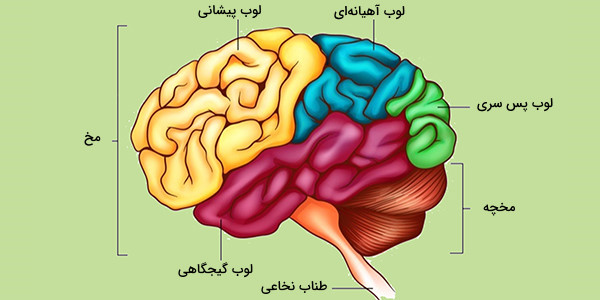

قیمت: 42٬000 تومان - دسته بندی فایل: پاورپوینتپاورپوینت قشر مخ

فروش ویژه پاورپوینت حرفه ای قشر مخ با تخفیف استثنایی فقط 54 هزار تومان تعداد اسلاید : 16 اسلاید